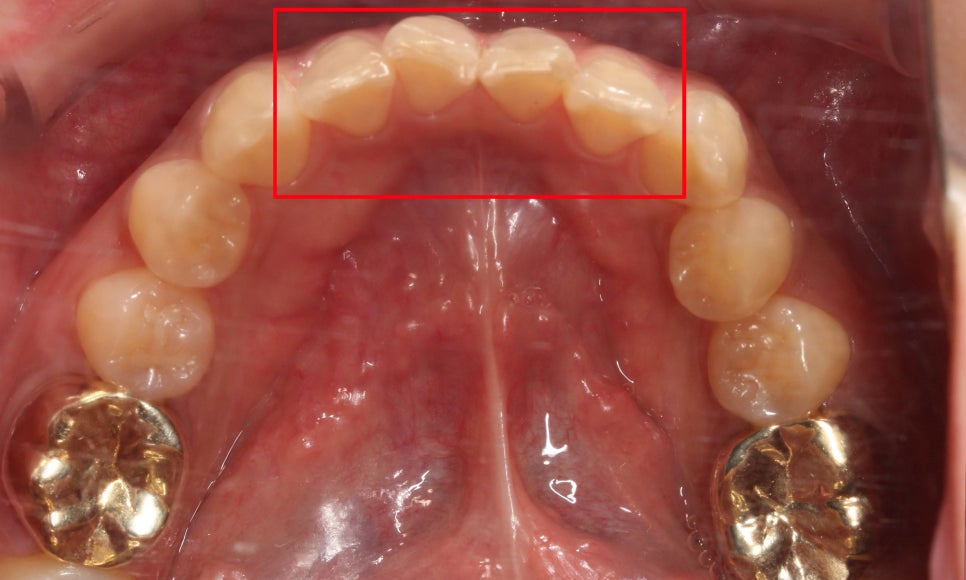

상악의 치아 배열을 보시면

중절치가 토끼앞니 증상으로

뻐드러져 있는 것을 볼 수 있는데요,

PFM크라운으로 수복된 앞니가

주변 자연치 부분과 어울리지 못하고

이질적인 느낌이 드는 모습입니다.

아랫니의 경우 전치부의 총생으로 인해

치아가 삐뚤어 보이는 모습인데요,